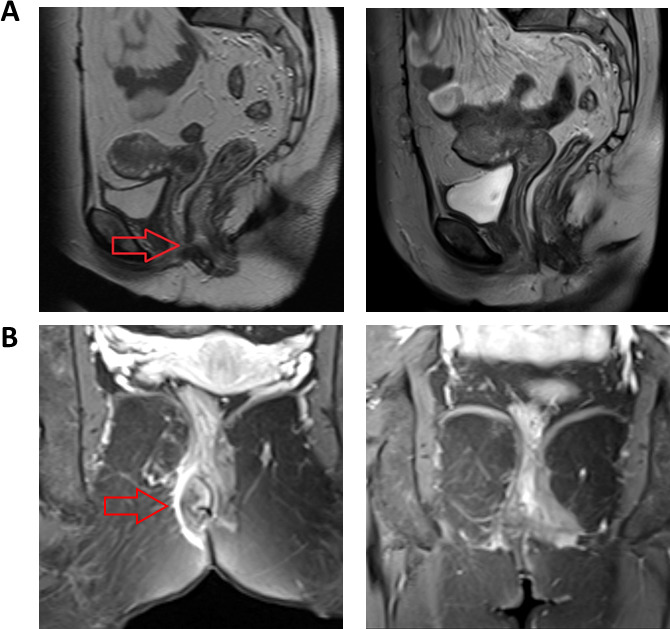

Results: Six female patients with a total of 13 fistulas (9 trans-sphincteric, 2 extrasphincteric and 2 rectovaginal) underwent bmMSC application. Median radiological and clinical long-term follow-up was 80 months (range 44-98 months) after first local bmMSC injection. 8 of 13 fistulas (62%) exhibited complete closure. For rectovaginal fistulas, long-term remission (98 months) was 50% (1 of 2). Pelvic MRI showed a decrease in modified Van Assche index from baseline to long-term follow-up. No immediate adverse events related to bmMSC injections were observed. One patient was diagnosed with a local adenocarcinoma of the rectum 106 months after first bmMSC injection. MRI control 11 months prior showed complete fistula remission. The tumour exhibited a female karyotype, while bmMSC had been derived from a male volunteer.